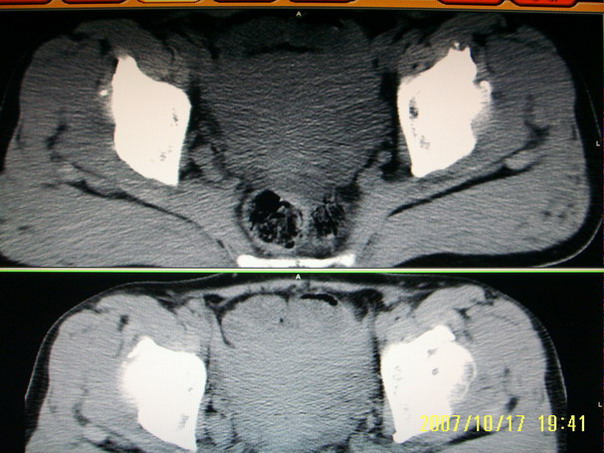

标题: CT10352:女,45岁,股骨头病变,如何诊断?

股骨头病变,如何诊断?

患者女,45岁,左髋部行走疼痛一年,无外伤史,无感染史。x片示囊状骨透亮区

股骨头形态尚可,骨皮质环厚度及完整性可,病灶区以外骨质尚未见明显异常,临近髋臼骨质亦可见类似改变,考虑退变性关节面下囊变可能性大,骨样骨瘤等不排除,

股骨头形态尚可,骨皮质环厚度及完整性可,病灶区以外骨质尚未见明显异常,临近髋臼骨质亦可见类似改变,考虑1.动脉瘤样骨囊肿,2.股骨头缺血坏死,

股骨头形态尚可,骨皮质环厚度及完整性可,病灶区以外骨质尚未见明显异常,临近髋臼骨质亦可见类似改变,考虑退变性关节面下囊变可能性大